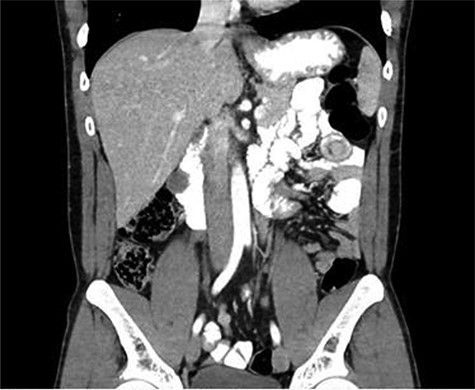

CT scan diagnosed 100% of the cases and all cases were reported as jejunojejunal (JJ) intussusception (Figs 1, 2). CT scan identified two patients having more than one intussuscepted segment. None of the patients were found to have lead points on imaging.

A 24-year-old female with CT scan with target sign in mid-right abdomen suggesting JJ intussusception